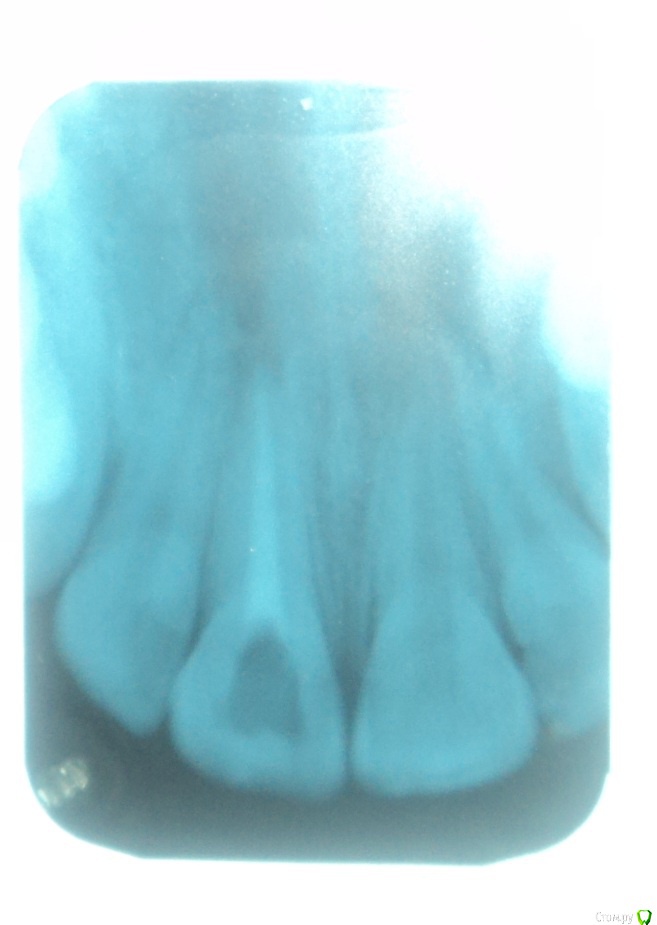

Здравствуйте! Примерно 12 лет назад у меня была травма переднего зуба после чего удалили нерв и  ввели в канал мне сказали метапекс, но по записям вроде не метапекс(фото с записями из карточки и снимки зуба прилагаю)  и запломбировали.  В течении примерно 10 лет (с 22.06.2005) этот зуб меня не беспокоил. Но в следствии ухудшения общего самочувствия я решил сходить к стоматологу. Мне сказали что у меня хронический периодонтит. У этого зуба посинела десна и это меня настораживает. Объясните мне в чем причина посинения десны? И я думаю что, то что происходит в этом зубе негативно сказывается на всем организме во первых как я думаю там может находиться очаг инфекции которая подрывает весь организм во вторых я почитал о действии на организм Метапекса( гидроокись кальция(гашеная известь)) и это действие очень не хорошее. Я не знаю что мне делать с этим зубом удалять или что то там менять чистить? Я не понимаю почему мне после стольких лет когда я пришел на прием мне ничего не сделали с этим зубом ничего не меняли и не чистили сказали все нормально и я ушел .так и должно быть? Жду ответа и совета врачей.

Удалять зуб не нужно. Снимок у Вас размытый получился, поэтому точнее сказать сложно. Посторайтесь либо перефотографировать снимок либо сделать новый.